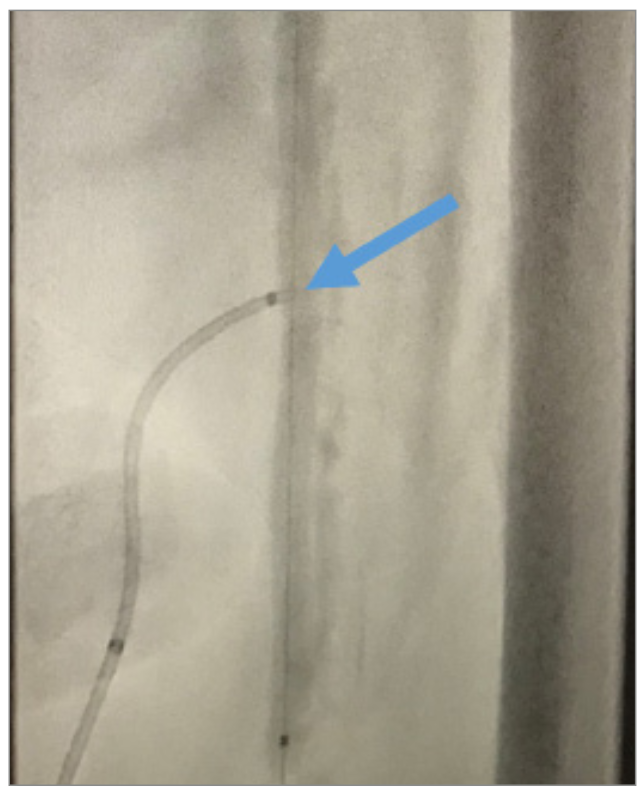

Internal tamponade of the left SFA access site was performed using a 4 × 150 cm Advance PTA balloon (Cook Medical) for 180 seconds, while removing the direct SFA access and Astato wire (Figure 5). We then turned our attention to the mid-SFA occlusion. An 18 g Victory wire (Boston Scientific) was used to cross the lesion, followed by a 3 × 40 mm, .014-inch LP balloon (Cook Medical), followed by a 5 × 200 mm Armada balloon (Abbott) to dilate the lesion (Figure 6). A dissection occurred in the SFA and popliteal arteries (Figure 7), so we placed a 6 × 250 mm Viabahn covered stent (Gore Medical) from the ostium to the distal SFA, and a 6 × 100 mm Zilver PTX stent (Cook Medical) was placed distal to the Viabahn covered stent, resulting in <10% residual stenosis and successfully tacking up the dissection (Figure 8). We then addressed the 99% distal popliteal/tibioperoneal (TP) trunk stenosis (Figure 9). We performed PTA of the TP trunk stenosis with a 4 × 28 mm Coronary Trek Balloon (Abbott), bringing the 99% stenosis to <20% residual stenosis (Figure 10) and improving the two-vessel flow to the foot (Figure 11).